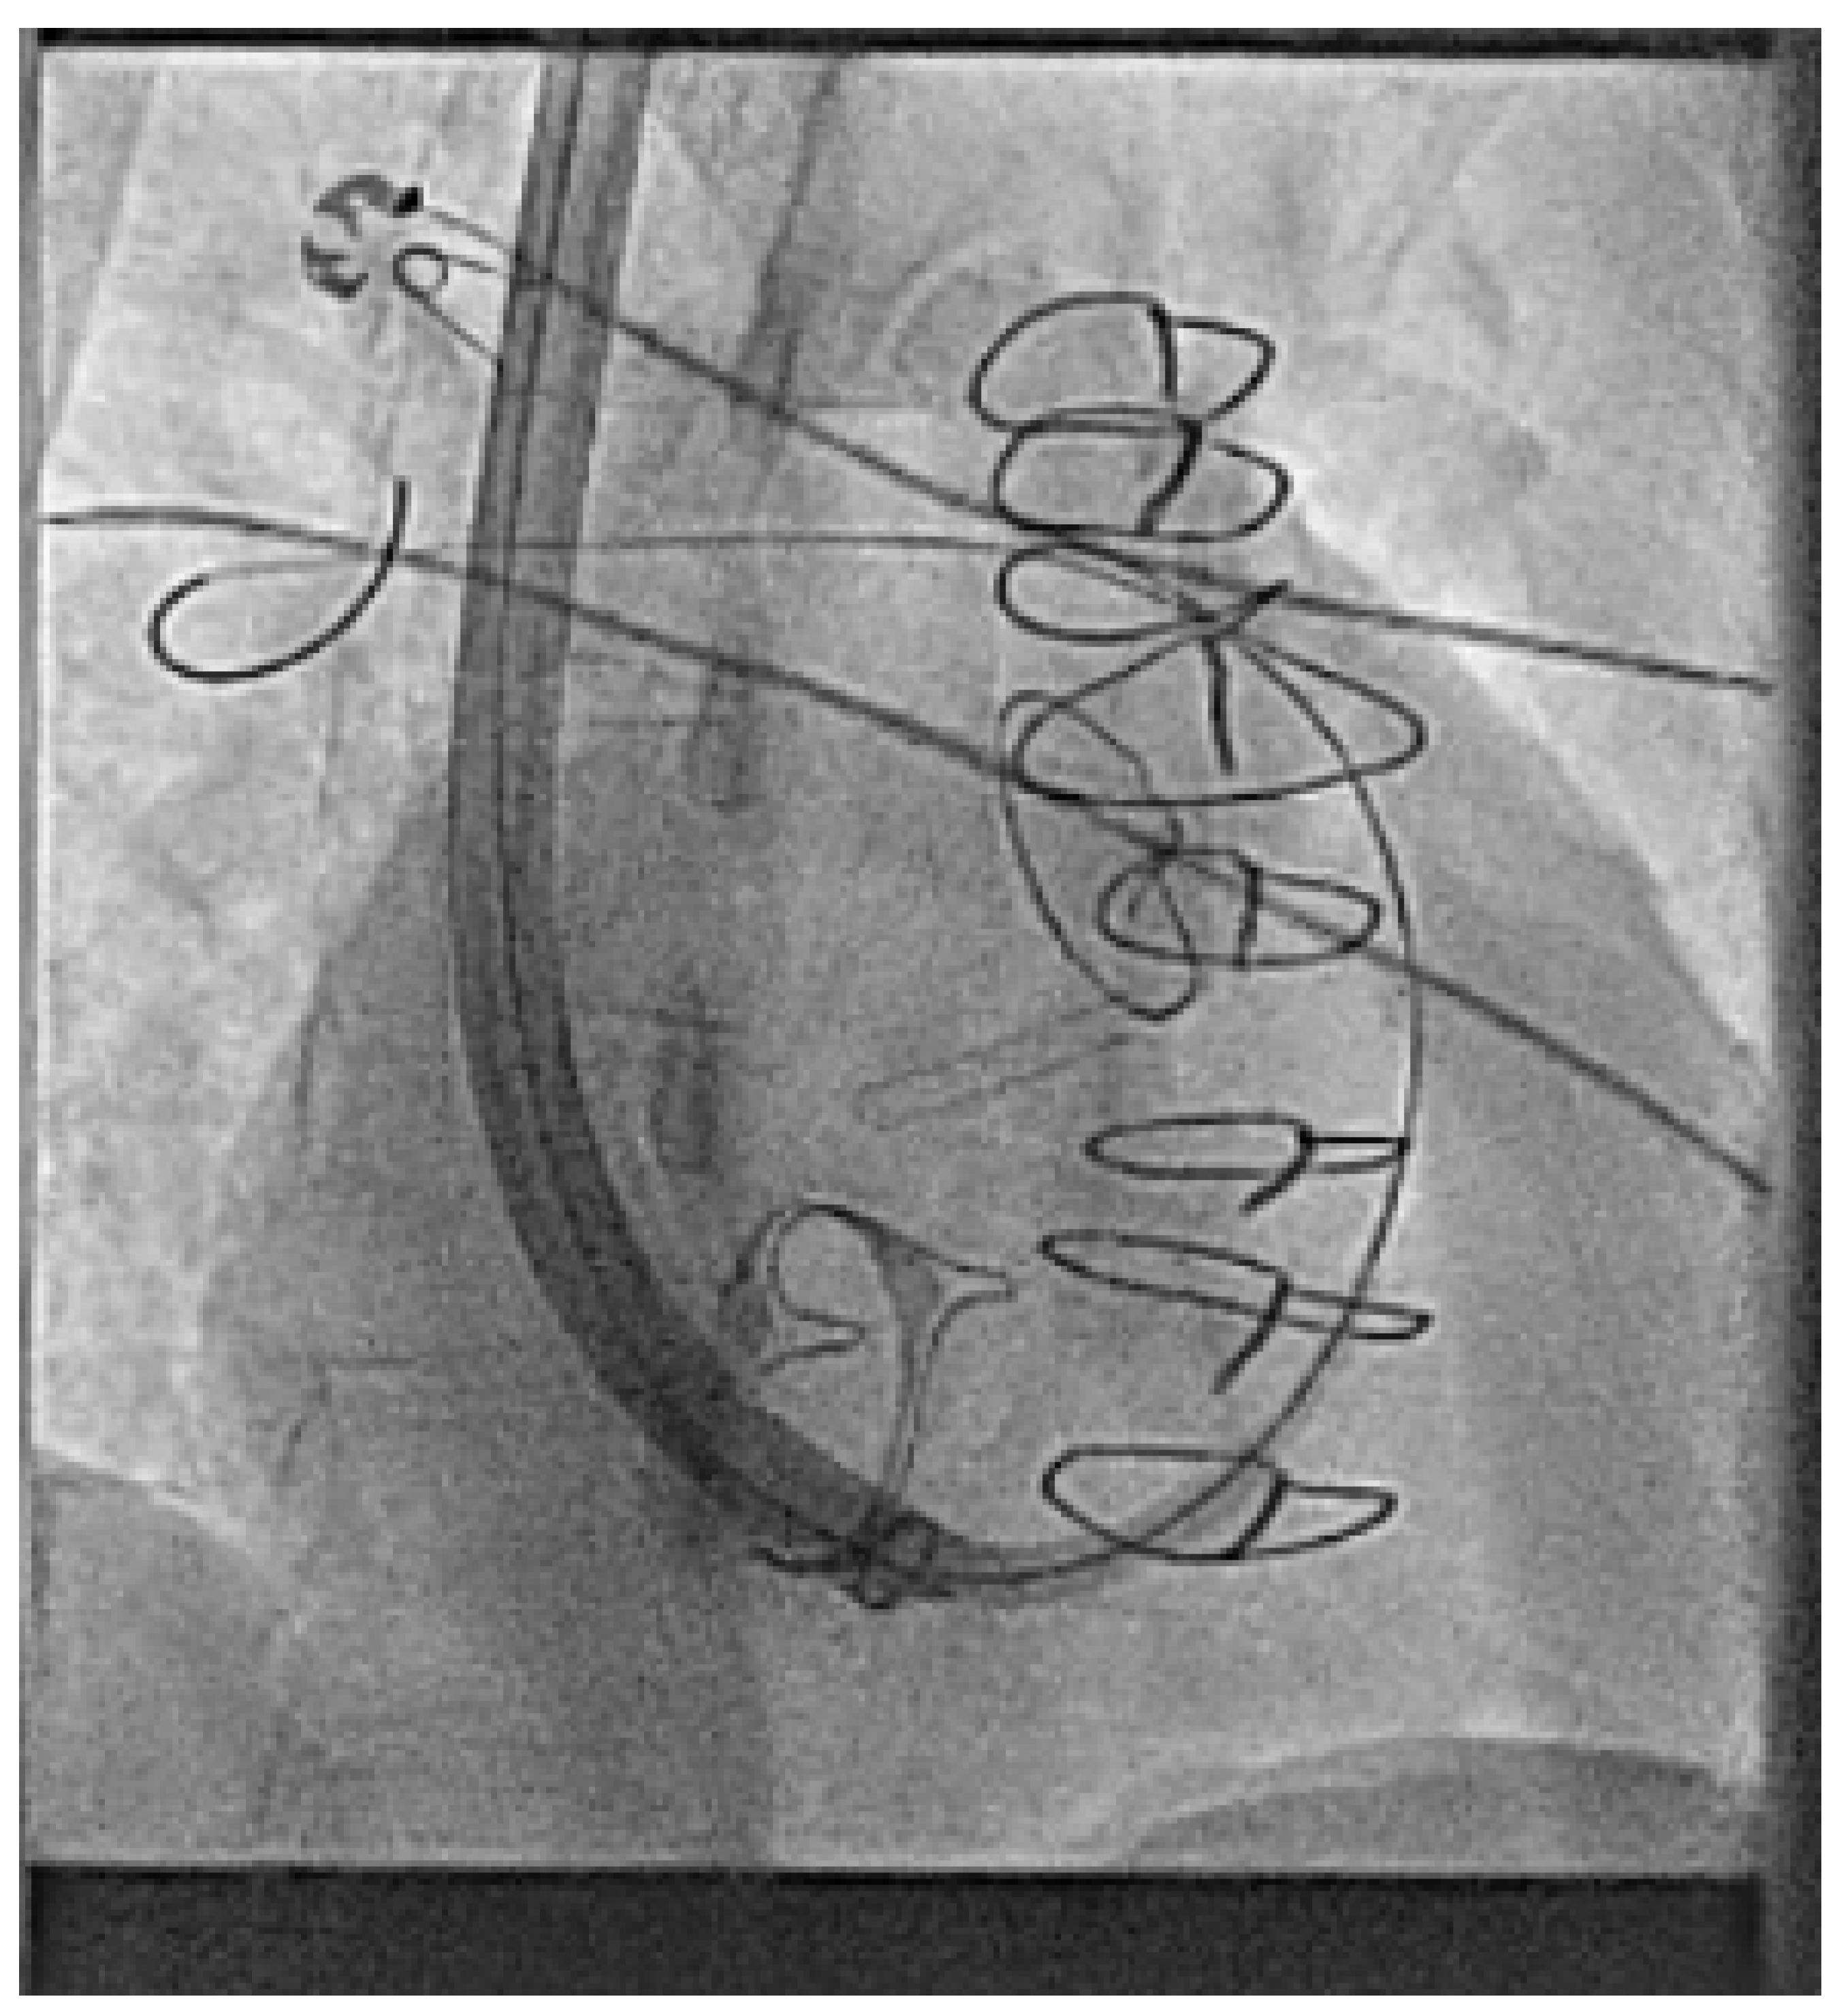

- Hayle, P.; Altayeb, F.; Hale, A.; Rao, A.; Ashrafi, R. Case report demonstrating novel approaches for leadless pacemaker implantation in the single ventricle heart. Eur. Heart J. Case Rep. 2025, 9, ytaf146. [Google Scholar] [CrossRef]

- Goulden, C.J.; Khanra, D.; Llewellyn, J.; Rao, A.; Evans, A.; Ashrafi, R. Novel approaches for leadless pacemaker implantation in the extra-cardiac Fontan cohort: Options to avoid leaded systems or epicardial pacing. J. Cardiovasc. Electrophysiol. 2023, 34, 2386–2392. [Google Scholar] [CrossRef]